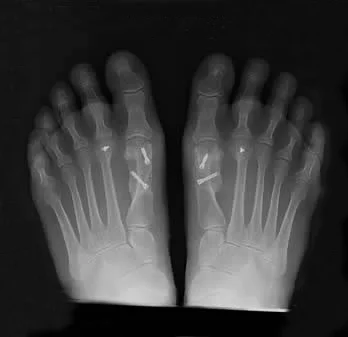

Hallux Valgus Bunion

Hallux Valgus (Bunion)

Your big toe joint has moved out of alignment. This causes the big toe to turn towards your second toe causing a bony bump to stick out at the side of your foot. This bump may have become red and sore and is known as a 'Bunion'. Read more >>